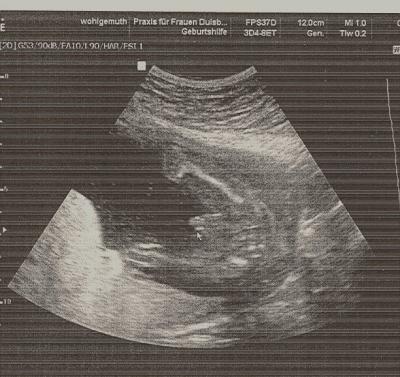

Huhu Mai Kugeln ab heute sind wir in der 22. Ssw Hier noch zwei Bilder von unserem kleinen Mann. Sieht man es nicht eindeutig das es ein kleiner Prinz wird? Euch noch einen tollen Tag Gruß Kati

Huhu, Da hast du ja ein seeehr eindeutiges beweißfoto von deinem prinzen Ich glaube, da verschwinden alle zweifel am geschlecht...... Gratulation noch zum kleinen mann. Ich komme am donnerstag in die 22.ssw Lg sandy

Tolles Bild, wird eindeutig ein Junge. Herzlich Glückwunsch zum Bub :-)